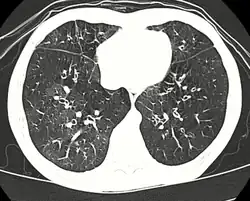

Medical imaging

Early in the disease chest radiography is typically normal but may show hyperinflation.[6] As the disease progresses a reticular pattern with thickening of airway walls may be present.[4][6] HRCT can also show air trapping when the person being scanned breathes out completely; it can also show thickening in the airway and haziness in the lungs.[11] A common finding on HRCT is patchy areas of decreased lung density, signifying reduced vascular caliber and air trapping. This pattern is often described as a "mosaic pattern", and may indicate bronchiolitis obliterans.[6]